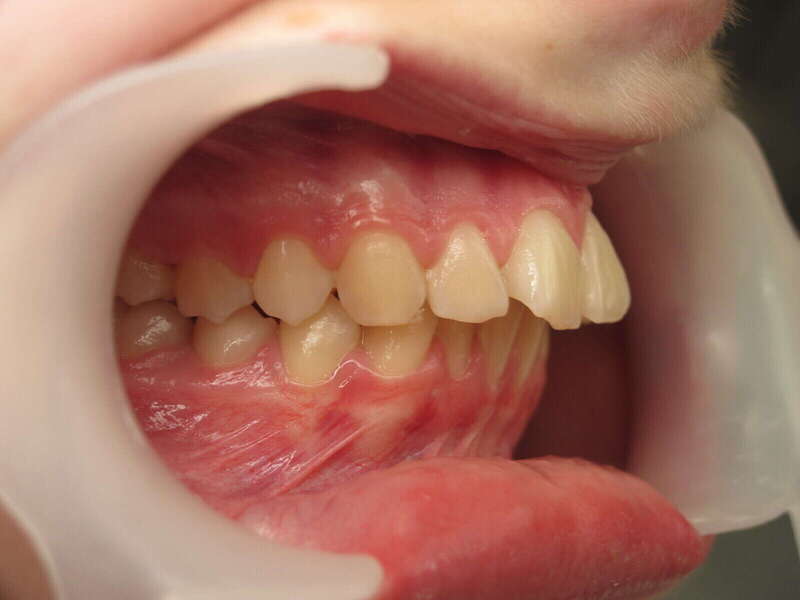

Ce cas d’interception chez un enfant de 8 ans démontre l'efficacité des aligneurs pour corriger des troubles fonctionnels précoces. Le diagnostic présentait des inversions d'articulé provoquant une déviation de la mandibule vers la gauche et un décalage des milieux.

Grâce à une coopération exemplaire et un traitement totalement indolore, l'expansion de l'arcade a permis de recentrer la mâchoire. Cette intervention a littéralement remis la croissance sur les rails, neutralisant le risque d'asymétrie faciale squelettique.

• Correction fonctionnelle : Recentrage immédiat de la mandibule et des milieux inter-incisifs.

• Prévention : Création d'un environnement favorable pour les dents définitives à venir.

C'est une étape fondamentale qui simplifie l'avenir orthodontique du patient tout en garantissant un développement facial harmonieux.